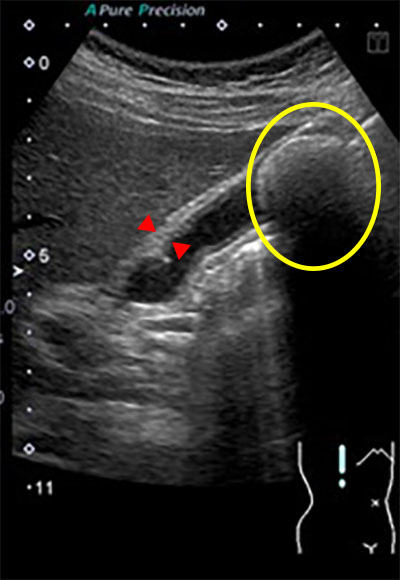

胆石、胆嚢炎の腹部超音波画像